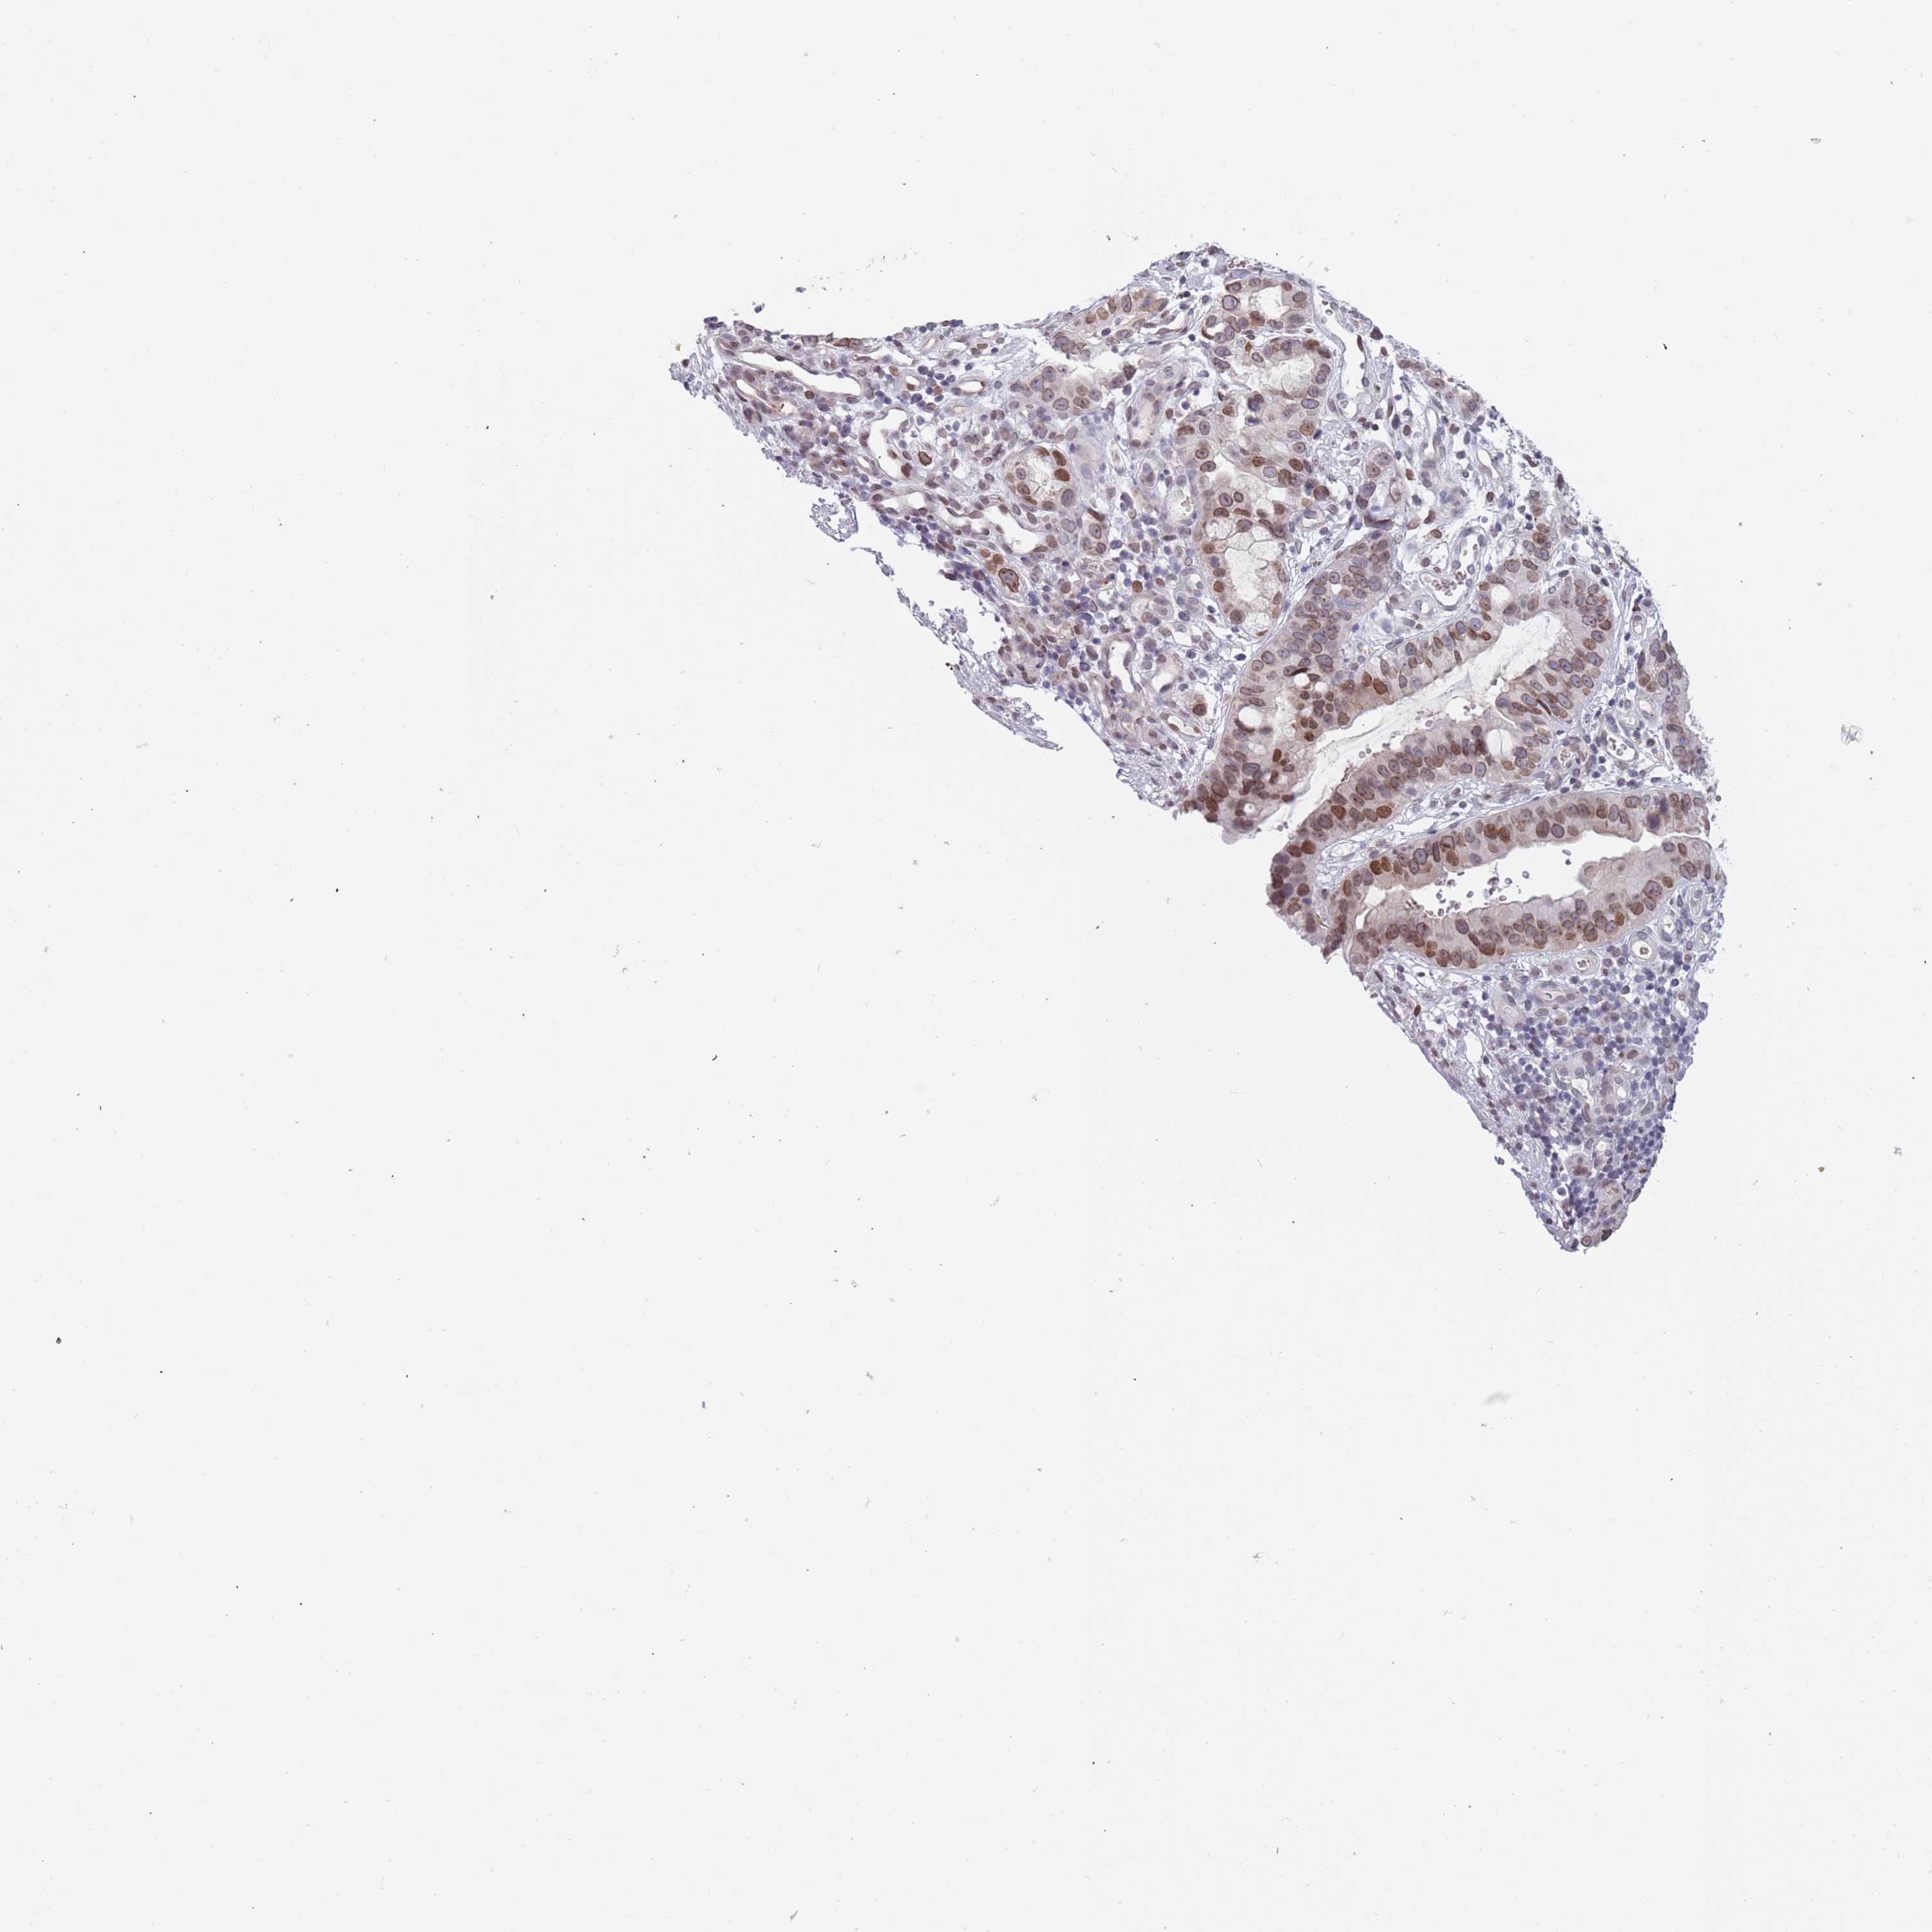

STOMACH CANCER - Protein expressioni

A mouse-over function shows sample information and annotation data. Click on an image to view it in a full screen mode. Samples can be filtered based on level of antibody staining by selecting one or several of the following categories: high, medium, low and not detected. The assay and annotation is described here.

Note that samples used for immunohistochemistry by the Human Protein Atlas do not correspond to samples in the TCGA dataset.

Antibody stainingi

Antibody staining in the annotated cell types in the current human tissue is reported as not detected, low, medium, or high, based on conventional immunohistochemistry profiling in selected tissues. This score is based on the combination of the staining intensity and fraction of stained cells.

Each image is clickable and will lead to virtual microscopy that enables deeper exploration of all samples and also displays staining intensity scores, fraction scores and subcellular localization as well as patient and tissue information for each sample.

Antibody HPA000628

Staining

High

Medium

Low

Not detected

Intensity

Strong

Moderate

Weak

Negative

Quantity

>75%

75%-25%

<25%

None

Location

Nuclear

Cytoplasmic/membranous

Cytoplasmic/membranous,nuclear

Adenocarcinoma, NOS